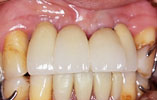

CASE3

下の奥歯2本が欠損 機能的回復

インプラント埋入前

インプラント埋入後

インプラントに

セラミッククラウンを装着

奥歯が2本失われ、従来は取り外し式の部分入れ歯を入れていました。2本のインプラントを埋入し、自分の歯と同様の感覚の「固定式」人工歯を入れ、噛む機能を回復しました。